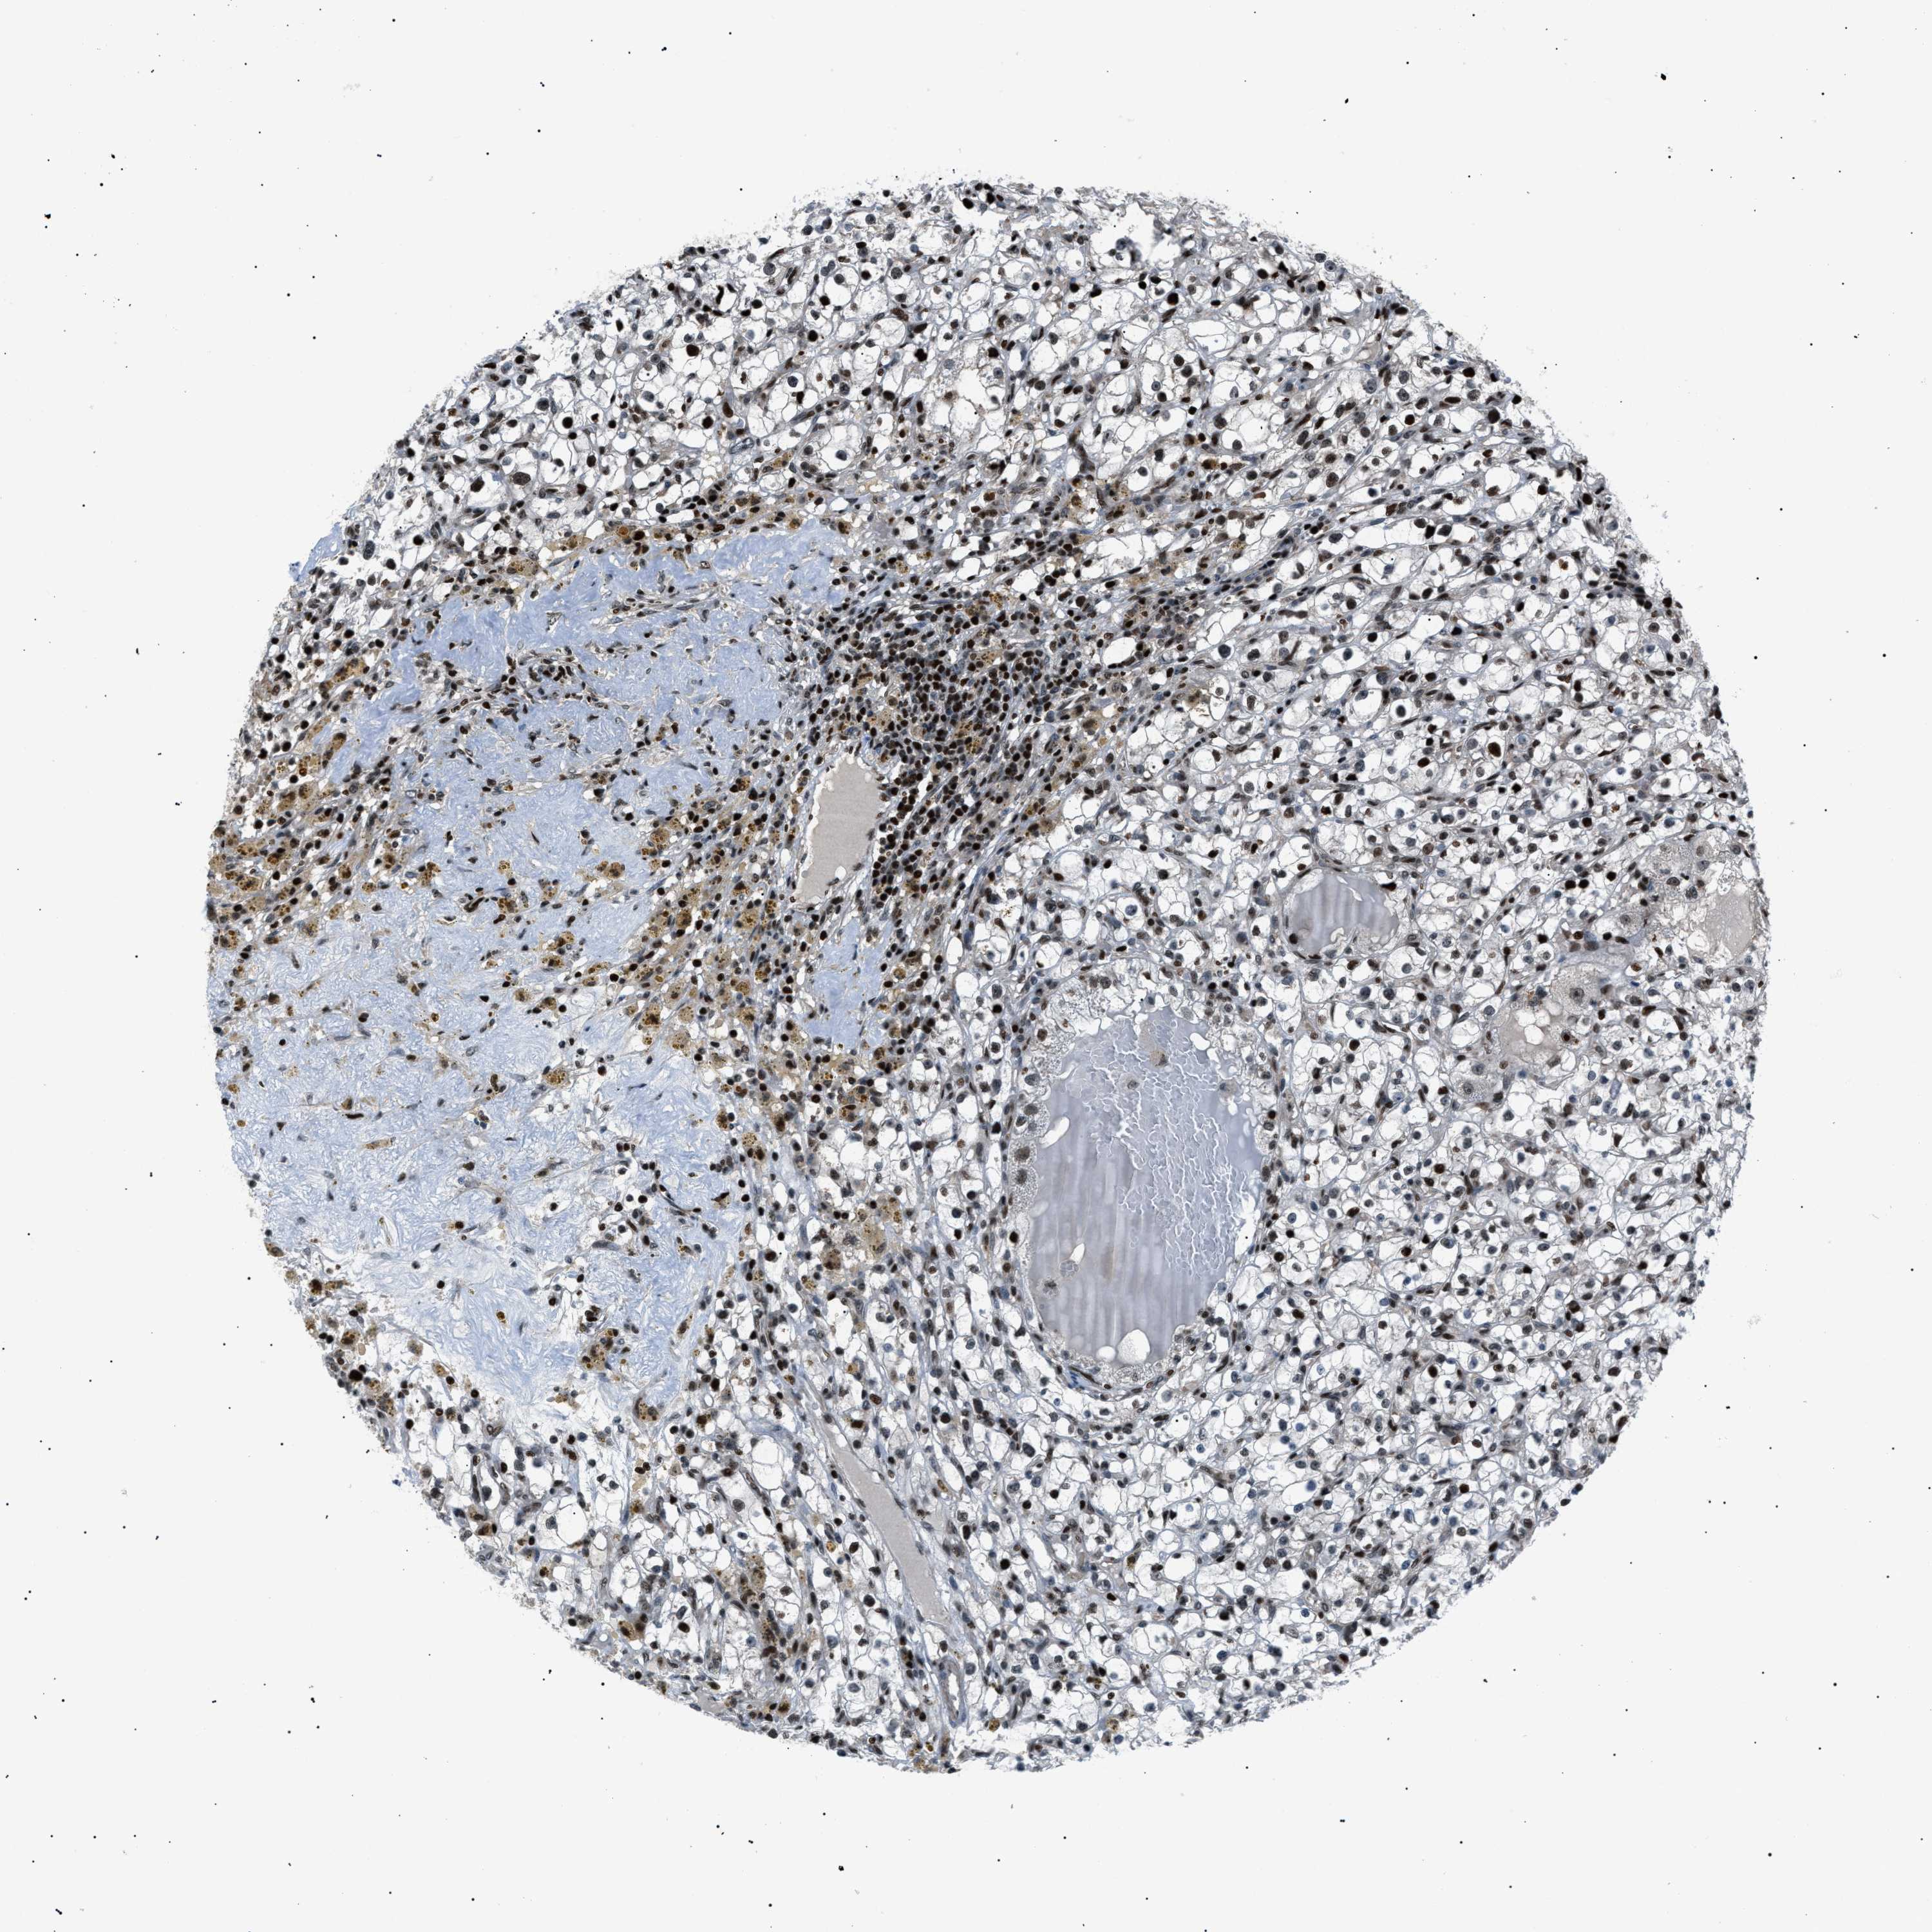

KIDNEY RENAL CLEAR CELL CARCINOMA (VALIDATION) - Interactive survival scatter ploti

The Survival Scatter plot shows the clinical status (i.e. dead or alive) for all individuals in the patient cohort, based on the same data that underlies the corresponding Kaplan-Meier plots. Patients that are alive at last time for follow-up are shown in blue and patients who have died during the study are shown in red.

The x-axis shows the expression levels (FPKM) of the investigated gene in the tumor tissue at the time of diagnosis. The y-axis shows the follow-up time after diagnosis (years). Both axes are complimented with kernel density curves demonstrating the data density over the axes. The top density plot shows the expression levels (FPKM) distribution among dead (red) and alive patients (blue). The right density plot shows the data density of the survived years of dead patients with high and low expression levels respectively, stratified using the cutoff indicated by the vertical dashed line through the Survival Scatter plot. This cutoff is automatically defined based on the FPKM cutoff that minimizes the p-score. The cutoff can be changed by dragging the vertical line or by entering a cutoff value in the square labeled "Current cut-off".

Under the Survival Scatter plot the p-score landscape (black curve; left axis) is shown together with dead median separation (red curve; right axis). Dead median separation is the difference in median mRNA expression between patients who have died with high and low expression, respectively. It is calculated as follows: median FPKM expression of dead patients with high expression - median FPKM expression of dead patients with low expression. This is intended to aid the user in visually exploring custom cutoffs and the associated p-scores and dead median separation.

Individual patient data is displayed and can be filtered by clicking on one or more of the category buttons on the top of the page. Categories describing expression level and patient information include: high, low, alive, dead, female, male and tumor stages. The scale of the x-axis can be toggled between linear and log-scale by clicking on the "x log" button. Mouse-over function shows TCGA ID, patient information and mRNA expression (FPKM) for each patient.

& Survival analysisi

Kaplan-Meier plots summarize results from analysis of correlation between mRNA expression level and patient survival. Patients were divided based on level of expression into one of the two groups "low" (under cut off) or "high" (over cut off). X-axis shows time for survival (years) and y-axis shows the probability of survival, where 1.0 corresponds to 100 percent.

PRKX is not prognostic in Kidney Renal Clear Cell Carcinoma (validation)

Best expression cut offi

: 8.82